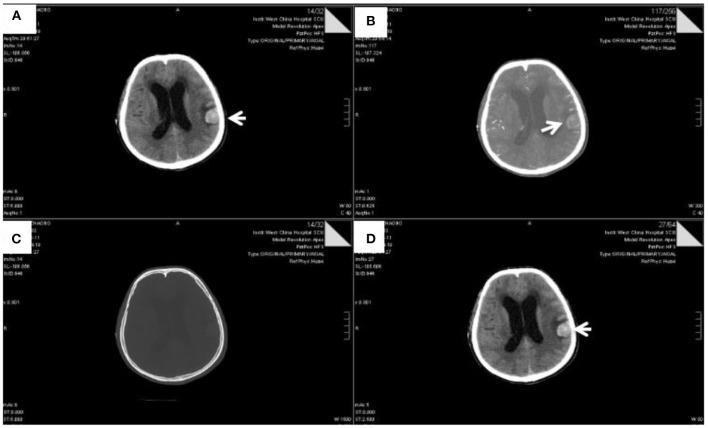

是临床实践中很少遇到的一种细菌。它是一种罕见的革兰氏阴性杆状细菌,与肺部和尿路感染有关,但从未在脑脊液中发现。本文报告了一例成年患者通过未知感染途径感染 导致严重颅内感染的病例。通过脑脊液培养和宏基因组下一代测序检测到了 。早期识别该菌株并用敏感抗生素进行治疗对于降低发病率和死亡率是必要的。一名24岁男性因头痛和呕吐2个月入住华西医院。症状特征包括起病急和病程长。值得注意的是,头痛和呕吐是主要的神经系统症状。常规脑脊液培养未能鉴定出该细菌;然而,通过第二代测序技术检测到了 细菌。发现 是一种多重耐药菌,因此,使用颅内感染常用药物头孢曲松治疗无效。该菌株最终导致严重颅内感染,致使患者死亡。总之,本研究全面描述了一例成年患者感染 的病例,并讨论了其早期识别以及在紧急情况下敏感抗生素的应用。